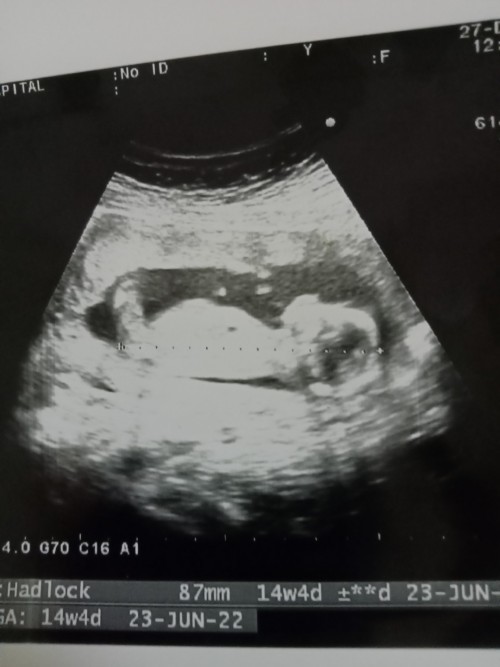

ภาพตอน14วีคค่ะ ตอนนี้16แล้ว #มิถุนา